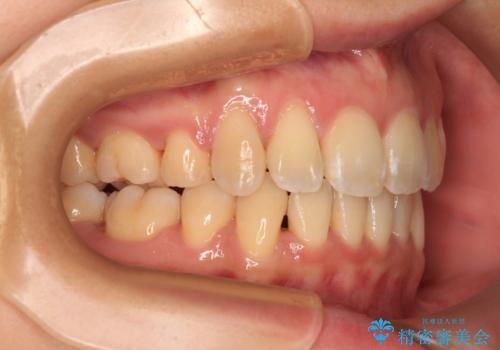

- 前歯の出っ歯と口元の閉じにくさを気にして来院された患者様です。

口元を積極的に引っ込めるために、上下左右の小臼歯4本を抜歯し、目立たないワイヤー装置にて矯正治療を行うこととしました。

上下前歯の歯軸の角度が大きく改善され、お口を閉じたときに顎先に認められた梅干し様の皺も改善されました。